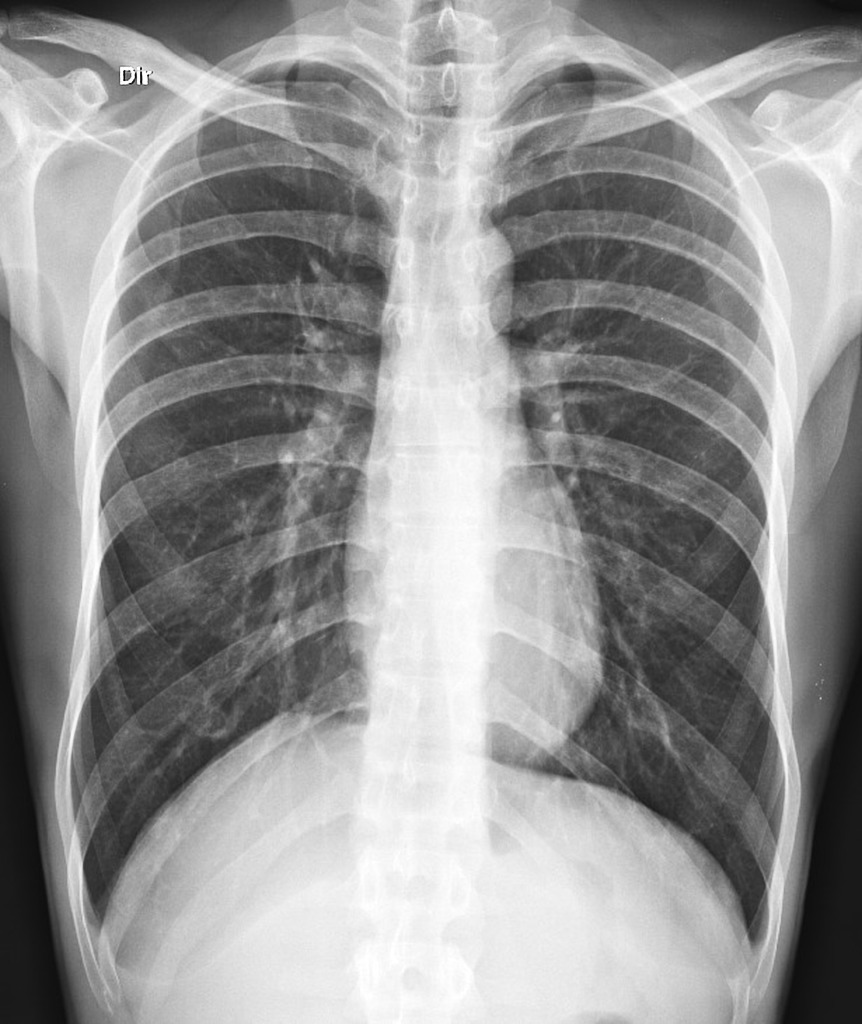

06. 엑스레이

영상 진단을 통해

정확한 문제부위를 확인합니다.